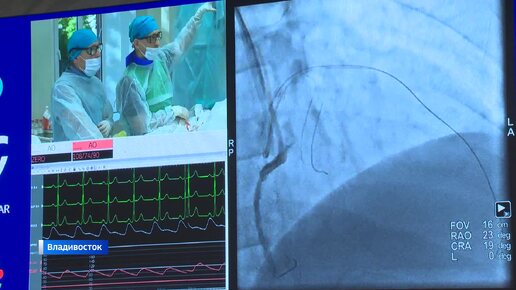

Врачи из разных регионов Сибири и Дальнего Востока приехали для обмена опытом во Владивосток